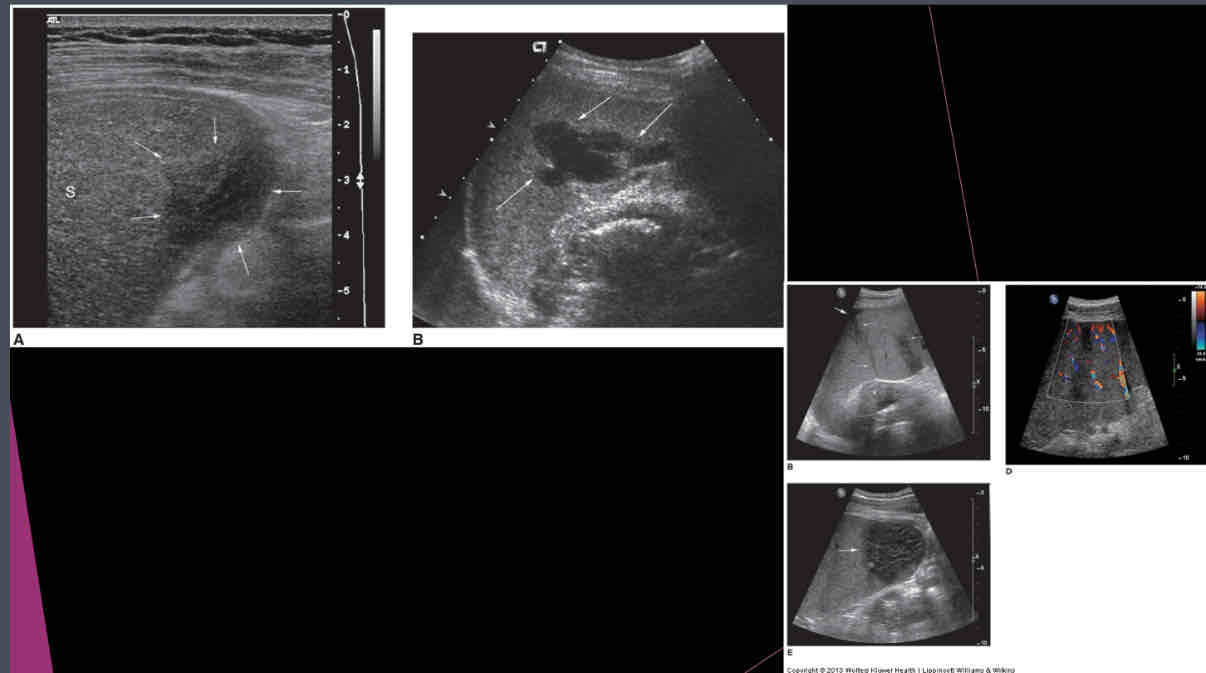

What does the following describe?

•Anechoic, well-defined walls, enhanced sound transmission

•Sharply demarcated wall, multilocular internal structure representing daughter cyst, mural calcifications

•Large cysts, dense, clearly defined walls May not have well-defined wall, mural calcifications Single or multiple simple cysts

splenic cysts

What are the different types of splenic cysts?

•Can be Congenital

•Can also be Acquired

• Echinococcal (hydatid)

•Epidermoid or epithelial

•Posttraumatic or postinflammatory pseudocysts

What does the following describe?

•Areas of tissue death, blood supply is cut off

•Found in patients with leukemia, sickle cell anemia, pancreatitis, bacterial endocarditis

•Calcification is last change

splenic infarct